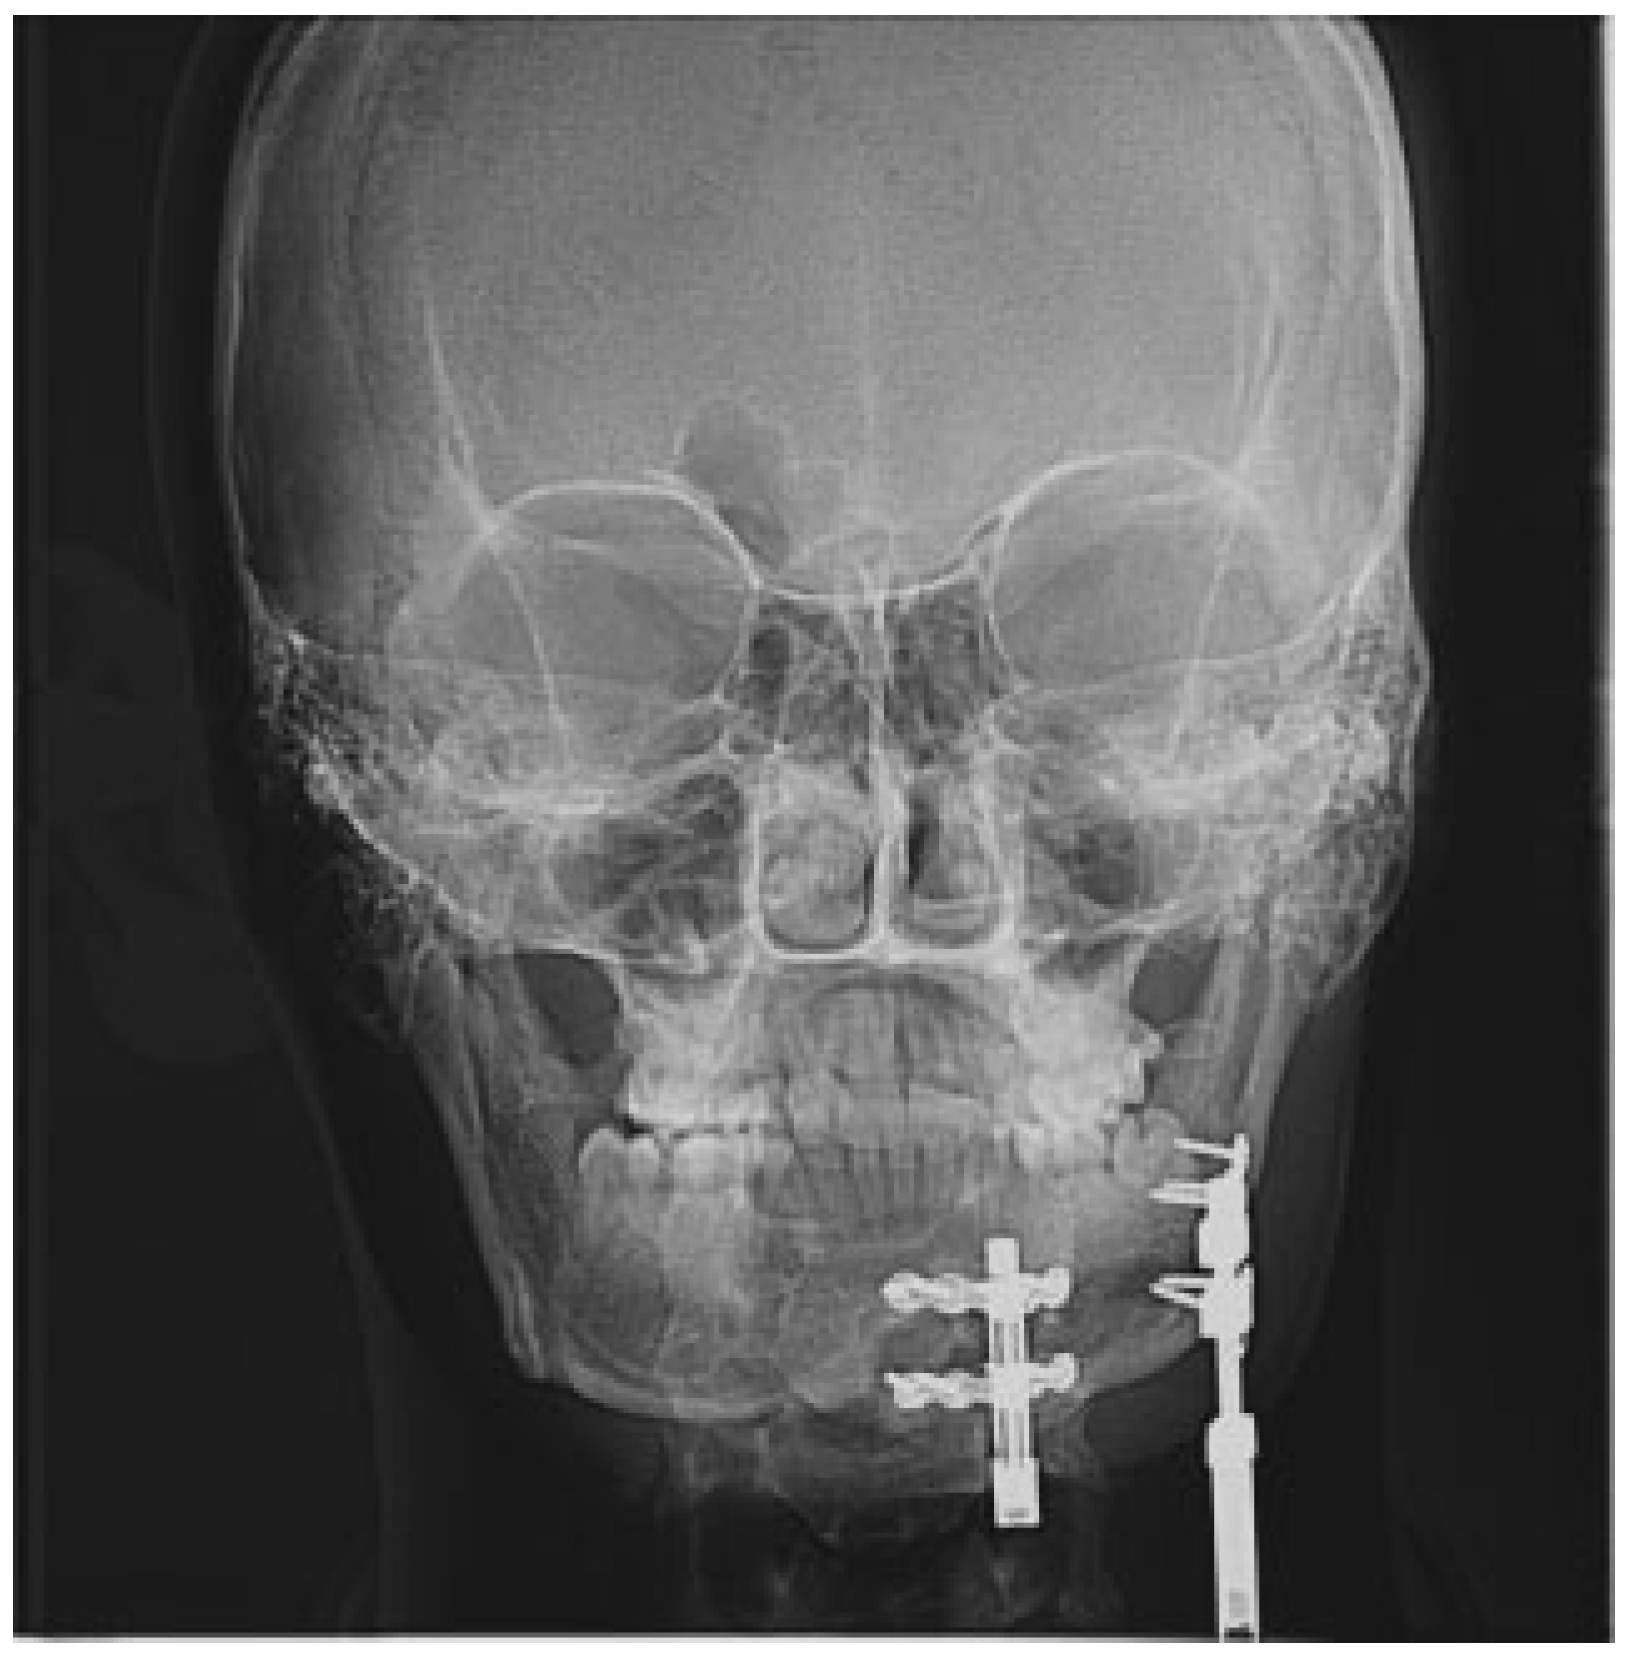

After a latency period of 5 days, distraction was started at the rate of 1 mm per day in twice daily rhythm. Total distraction of approximately 13 mm anteriorly and 7 mm posteriorly was achieved taking into account 30 to 40% overcorrection to overcome relapse (Figure 3). The bony correction achieved was seen as a remarkable improvement in the appearance of the patient (Figure 4).

Figure 3. PA skull radiograph showing the distractors in place.